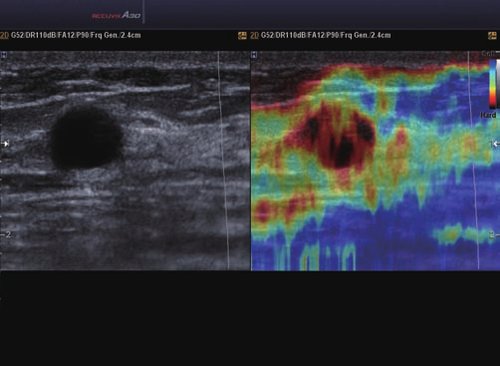

• ElastoScan™ ermöglicht eine genauere Visualisierung von Tumoren und erfasst und dokumentiert Gewebesteifheiten.

Das Ultraschallsystem hebt sich besonders durch seine 3D-Technologie wie die Face Auto Detection für detaillierte Ultraschallbilder von Föten oder das Volume Shade Imaging, das sich auf die lebensnahe Darstellung von Schattierungen und Hauttönen fokussiert, ab. Mit weiteren wertvollen Technologien wie dem ElastoScan™ werden Tumore schneller erfasst und durch die HD Volumen Bildgebung sowie das DMR+™ eine erstklassige Bildqualität erzielt.